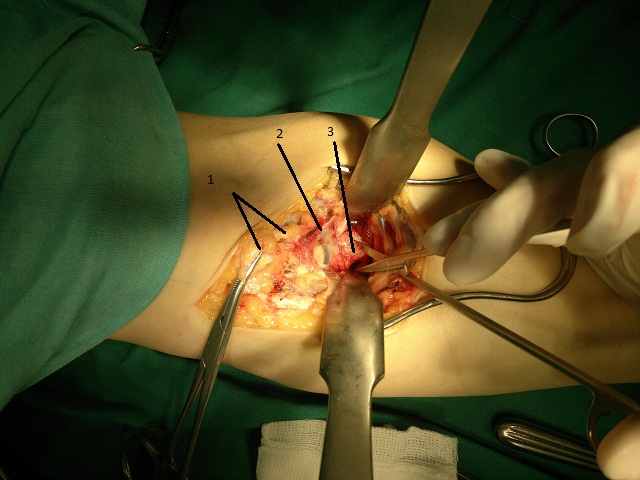

Потешу ваше любопытство сегодняшней операцией )))<br />Мужчина, 48 лет, профессионально занимается бодибилдингом, не курит.<br /><br />Впервые почувствовал "хруст" и боль в области локтевого сгиба во время тренировки около 3 месяцев назад, однако за медицинской помощью не обращался. Лечился самостоятельно путем эластичного бинтования в течение 4 недель. После чего снова начал тренироваться и при первой же нагрузке мышц-сгибателей предплечья почувствовал в очередной раз "щелчок" и острую боль. За медицинской помощью обратился спустя 2 месяца.<br /><br />Во время операции S-образным доступом в локтевой ямке выделено разорваное дистальное сухожилия бицепса, 10% волокон которого сохранили свою точку крепления, остальная часть сухожилия мышцы была спаяна с окружающими тканями (1). Выделена плечевая артерия на уровне бифуркации (2) и срединный нерв, а также область бугристости лучевой кости. На протяжении 2 см рассечена и отпрепарована надкостница (3) - предполагаемое место реинсерции. После чего в переднем кортикальном слое сделано отверстие для анкера, импактирован анкер, одной из нитей которого прошито сухожилие. После чего выполнено проведение дистального сухожилия бицепса под сосудисто-нервным пучком и нити связаны в положении сгибания в локтевом суставе до 90 градусов. Послойный шов, дренирование раны. Иод. Ас. повязка. Гипсовая лонгета в среднефизиологическом (или пронации) положении предплечья.<br /><br /><br />